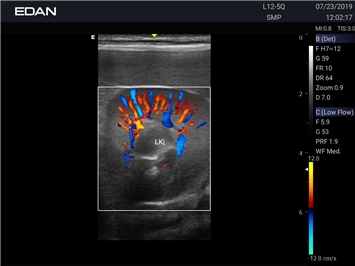

Энергетический допплер:

Да

Цветовой допплер:

Направленный энергетический допплер: